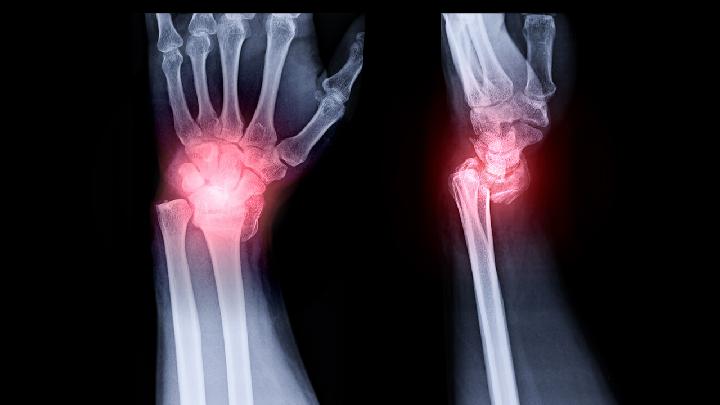

患者一旦发现患有骶髂关节炎,积极治疗是关键,治疗骶髂关节炎的方法有很多种,大多数患者可能并不了解,如果骶髂关节炎得不到有效的治疗往往会使病情加重,对患者的身体健康带来严重影响,下面我们就一起来了解一下怎么治疗骶髂关节炎。

骶髂关节炎的治疗可以从以下三个方面入手。

身体健康是一个人生活的最大财富,骶髂关节炎给患者带来了无穷的病痛折磨,一旦患了骶髂关节炎,在患病初期不易察觉引起患者的重视,但是到了患病后期疼痛和发病频率就会加重,严重的影响患者的生活和工作,那么,怎样诊断骶髂关节炎呢?

骶髂关节炎的发病原因有很多,同时骶髂关节炎的患病类型也有很多,只有我们通过不同的临床表现,准确的判断骶髂关节炎的类型,才能够对症下药,事半功倍。那么,骶髂骶髂关节炎是否能治愈?今天我们就一起来认识一下治疗方法。